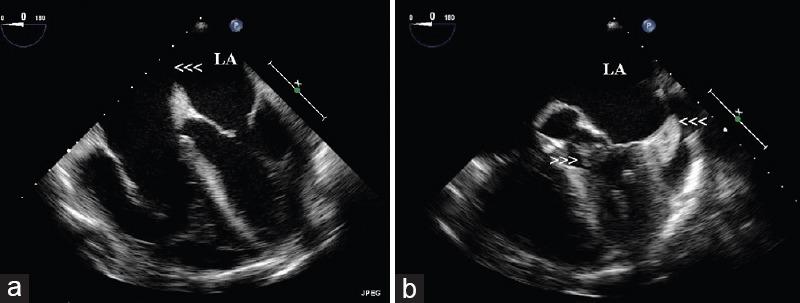

A 56-year-old male, who is an active intravenous drug abuser (IVDA) (heroin) with a history of diabetes, hypertension, chronic kidney disease, and hepatitis C-related liver cirrhosis, presented with generalized anasarca, bilateral pneumonic infiltrations, and heart failure. His blood cultures were positive for and were treated with antibiotics. Echocardiogram showed multiple uncommon manifestations of left-sided endocarditis. Surprisingly, he did not have right-sided involvement. Furthermore, echocardiogram revealed undiagnosed large atrial septal defect suggesting a paradoxical seeding of infective vegetation. This case illustrates the uncommon manifestations of endocarditis in an IVDA and indicates that it is very important to check comprehensively for an atrial septal defect or patent foramen ovale or any shunt in such high-risk patients who may be at risk for left-sided endocarditis which is catastrophic when compared to right-sided endocarditis. If detected early in IVDA patients, these shunts need to be closed to prevent paradoxical embolism of vegetation.

一名56岁男性,是活跃的静脉注射吸毒者(IVDA,使用海洛因),有糖尿病、高血压、慢性肾脏病和丙型肝炎相关肝硬化病史,出现全身水肿、双侧肺部浸润和心力衰竭。他的血培养 呈阳性,接受了抗生素治疗。超声心动图显示左侧心内膜炎有多种罕见表现。令人惊讶的是,他没有右侧受累。此外,超声心动图显示未诊断出的大型房间隔缺损,提示感染性赘生物的反常播散。该病例说明了IVDA中的心内膜炎的罕见表现,并表明对于这类可能有左侧心内膜炎风险(与右侧心内膜炎相比后果严重)的高危患者,全面检查房间隔缺损、卵圆孔未闭或任何分流非常重要。如果在IVDA患者中早期发现这些分流,需要进行封堵以防止赘生物的反常栓塞。